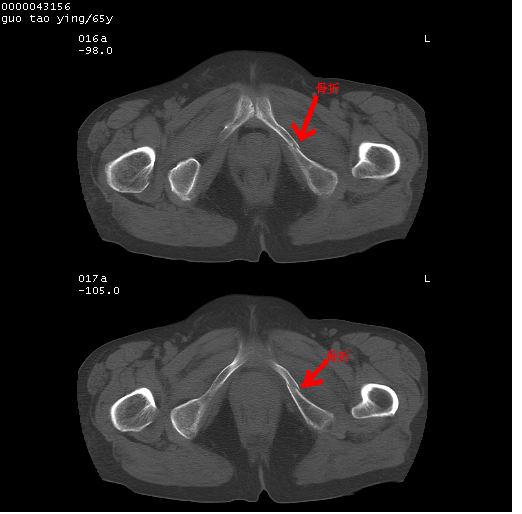

以下是引用黑白光影在2008-1-30 13:22:00的发言:[br]支持左耻骨骨折。[br]未见骶骨骨质明确破坏改变。[br]经楼主提示(勿局限于外伤)。考虑为右侧腹股沟直疝。[br][br][br][br]